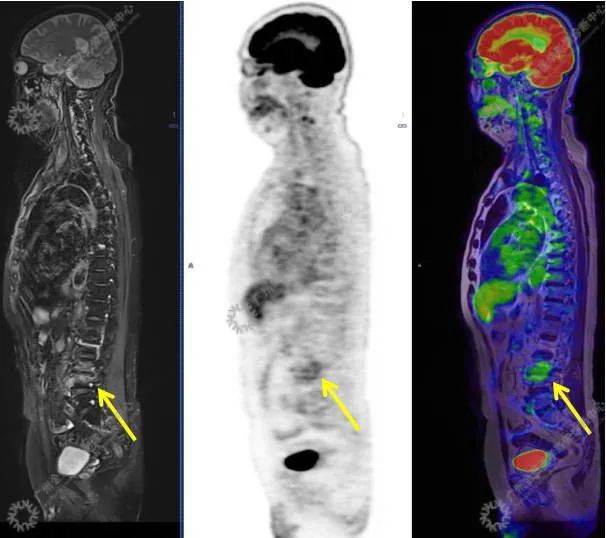

结合影像及实验室检查,临床最终考虑 IgG4 相关性疾病。

●18FDG-PET/CT 作为一种解剖和功能结合新的显像方法,IgG4-RD 的诊断及鉴别诊断中存在着巨大的优势:

●18FDG-PET/CT 扫描作为一种全身检查,有着传统影像学局部扫描无法比拟的优势,PET/CT 扫描不仅可以发现以临床症状为导向的局部病灶,更可以发现远隔部位的受累病灶。